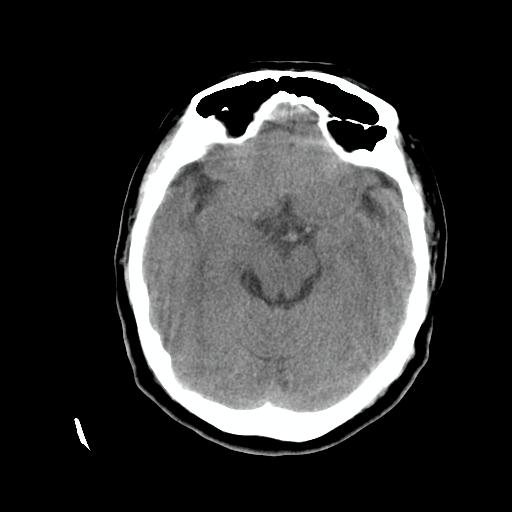

标题: CT24768:双侧脑室内囊性病变,主各位站友会诊。 [打印本页]

标题: CT24768:双侧脑室内囊性病变,主各位站友会诊。

患者女,62岁,临床提供头痛、头晕数月,无恶心及呕吐,近日加重。请各位站友看看,能否定为双侧脑室脉络丛囊肿,如果不能,应考虑什么?谢谢!

室管膜钙化 脑内多发钙化灶 可考虑寄生虫 结核等颅内感染

首选考虑---脑囊虫病。